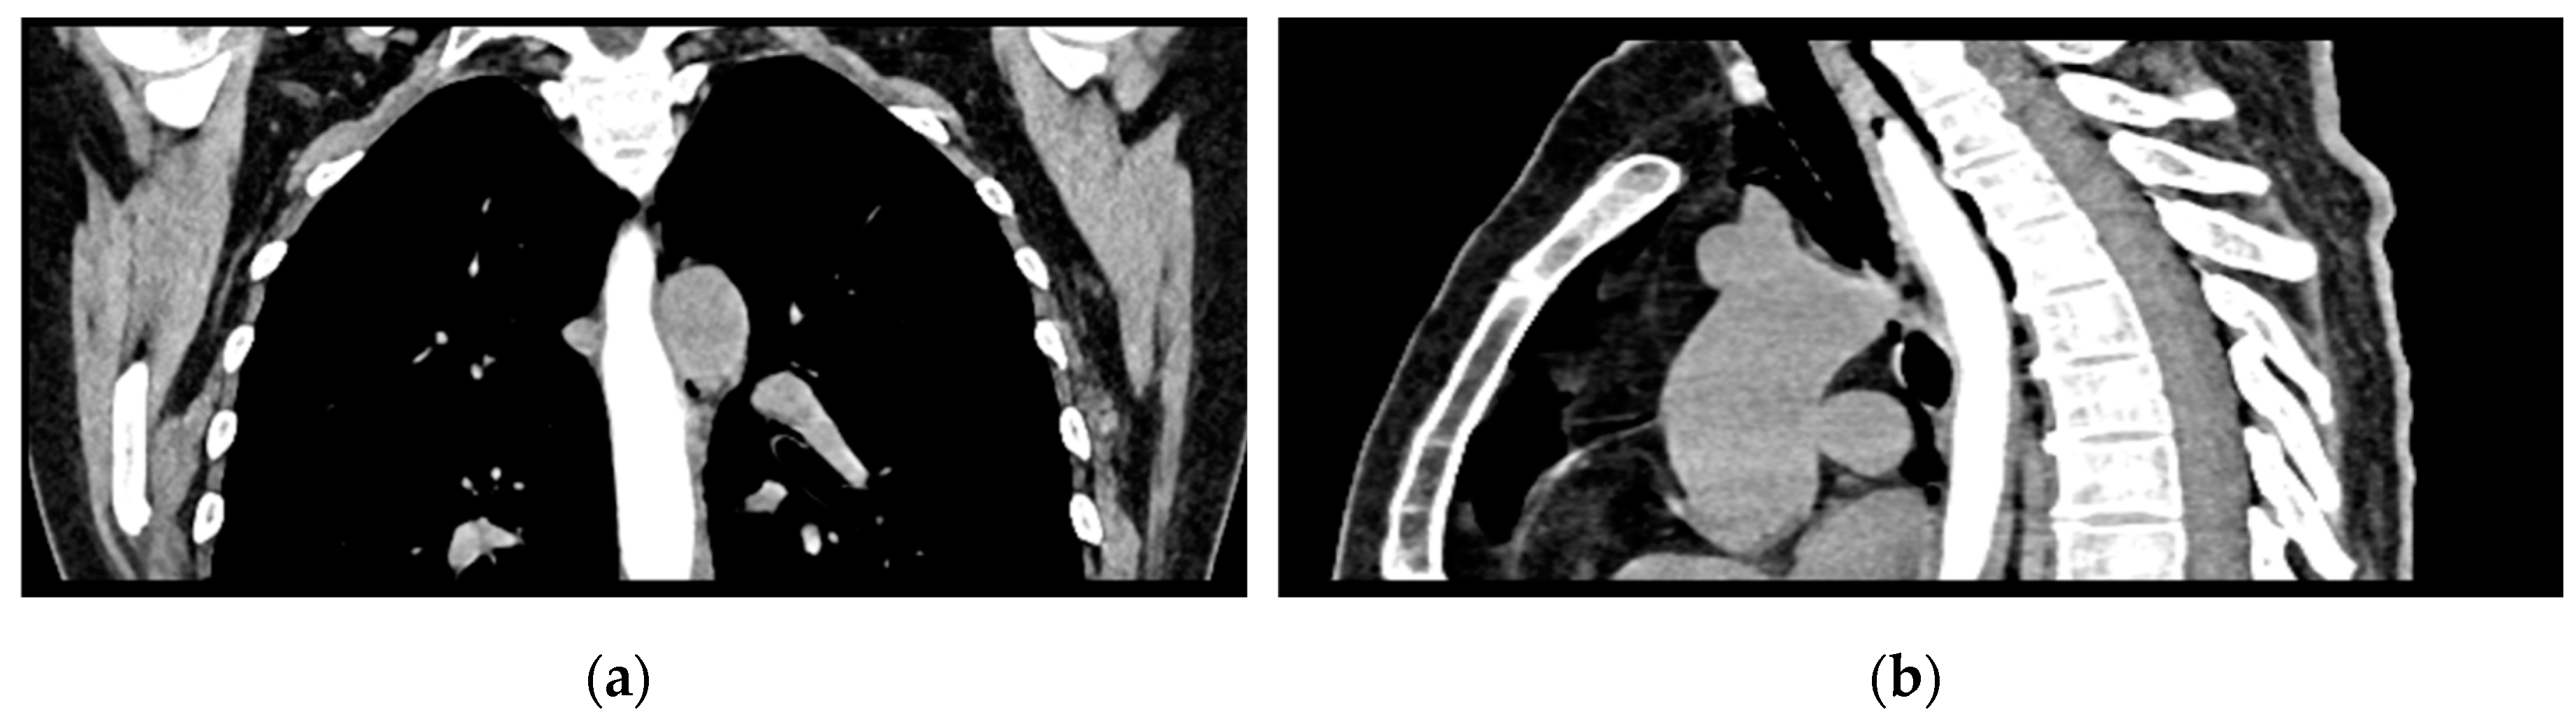

Given the patient’s history of vomiting, and consulting with the thoracic surgeon, a second CT scan with oral contrast was performed approximately 3 hours later, after initial stabilization of the patient, to rule out an oesophageal rupture. The subsequent imaging revealed the progression of the pneumomediastinum, with increased extension into the cervical region, including the peritracheoesophageal, perithyroidal, and retropharyngeal spaces (Figure 3), without evidence of oesophageal rupture (Figure 4). Oxygenotherapy and empiric antibiotherapy were initiated in the ED as initial treatments of this condition.

Figure 4. Oral contrast chest CT with no extravasation of the contrast substance: (a) coronal view; (b) sagittal view.